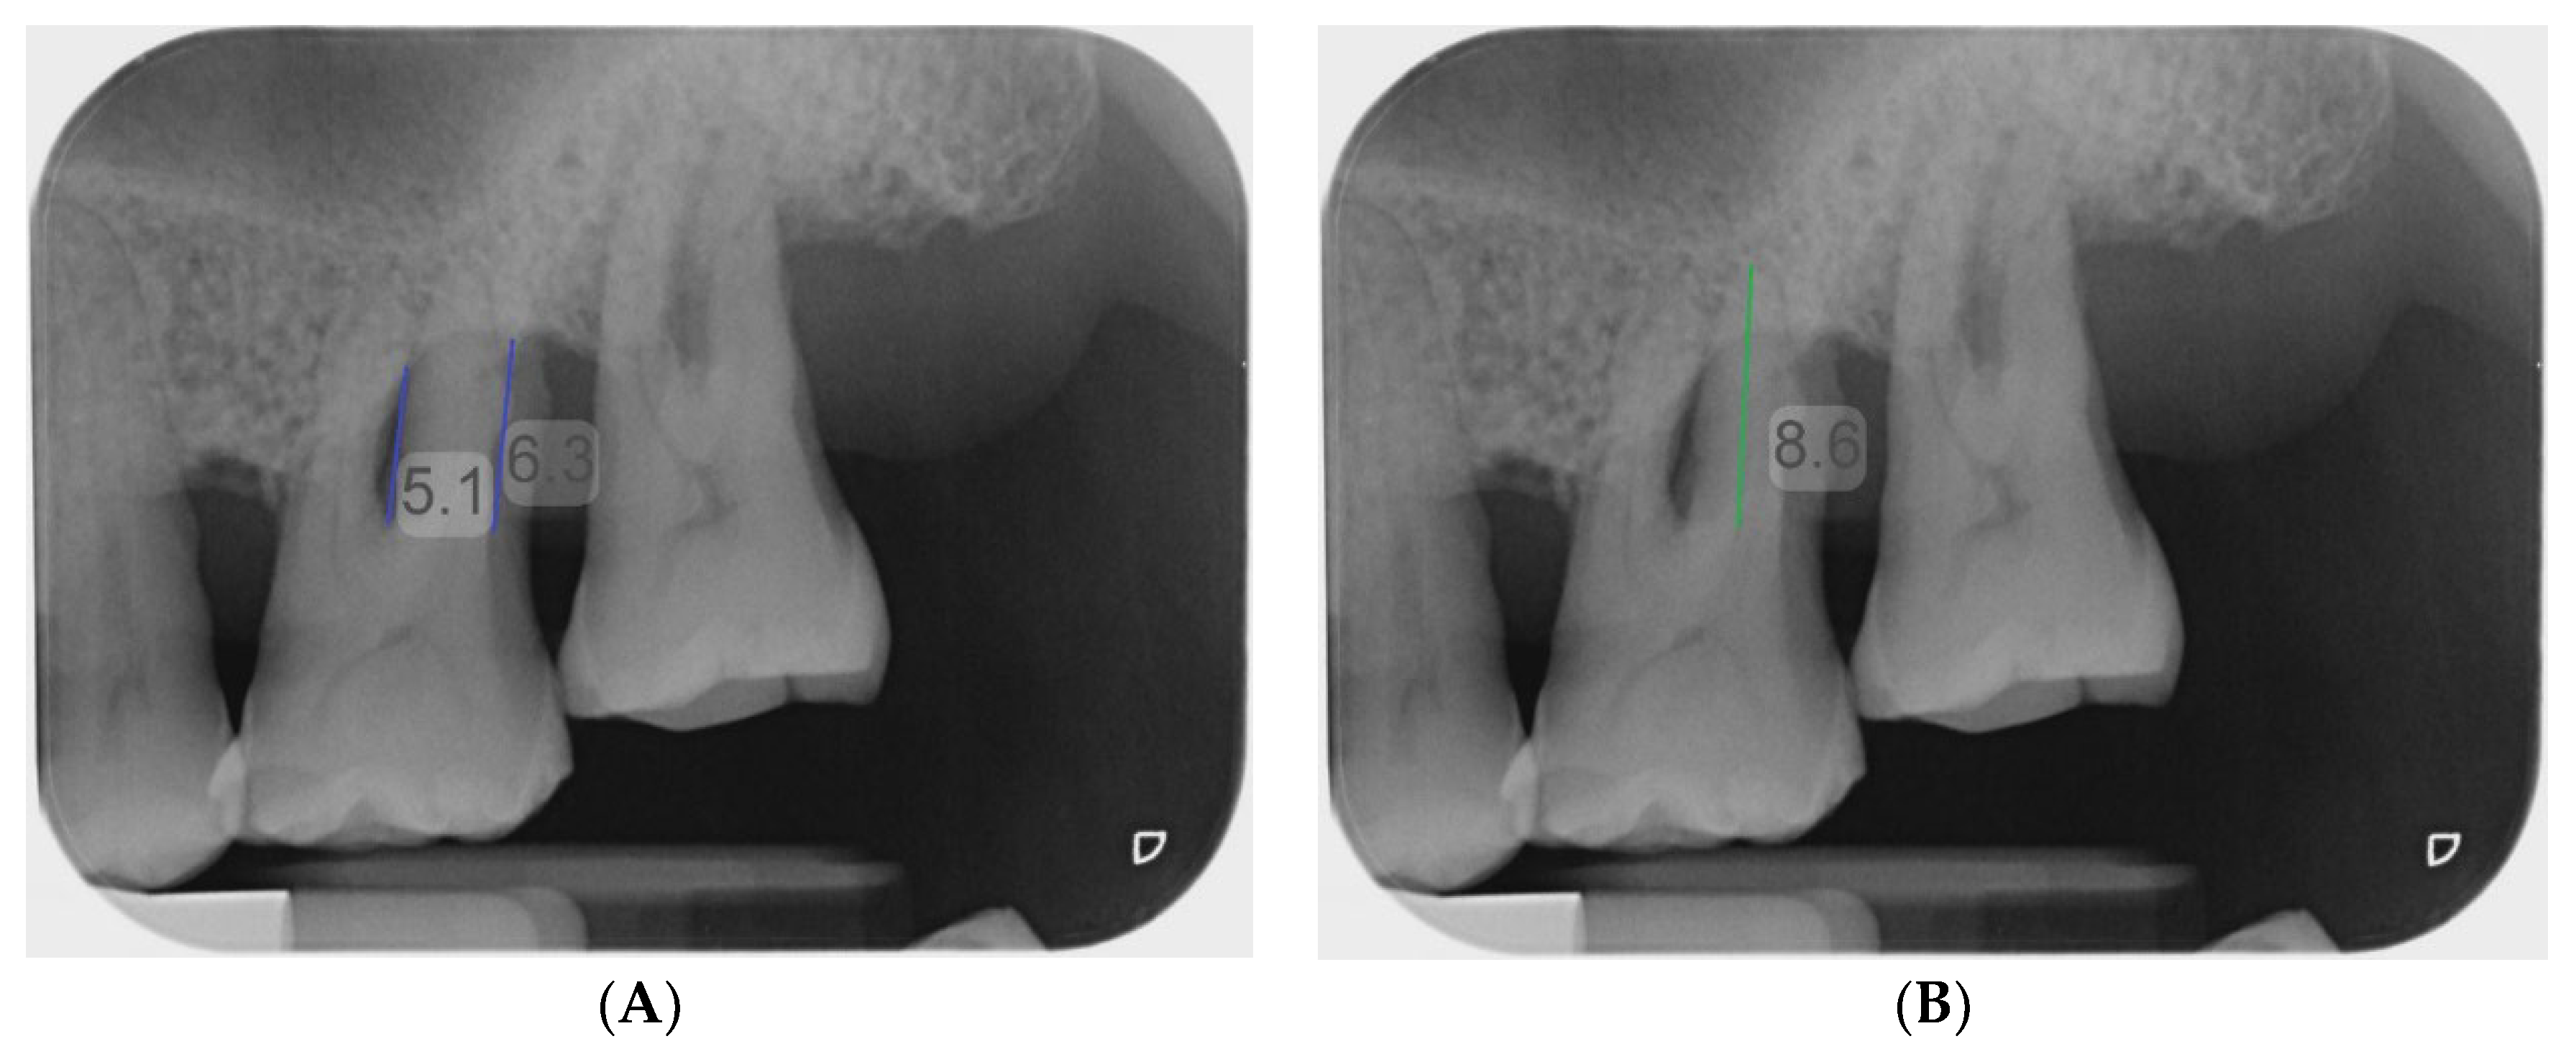

2.4. Gold Standard Assessment

2.5. Examiners and Image Analysis